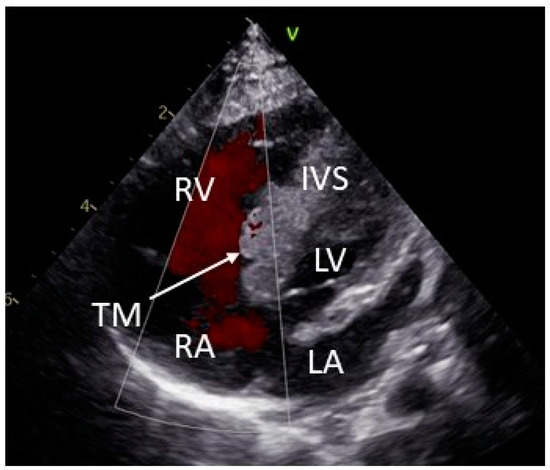

2. Case Description